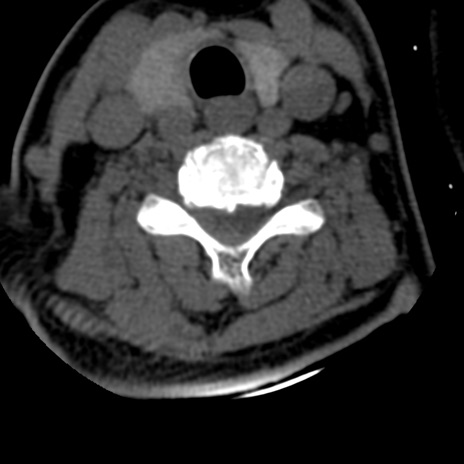

症例50 頚椎CT(横断像)

頚椎CT